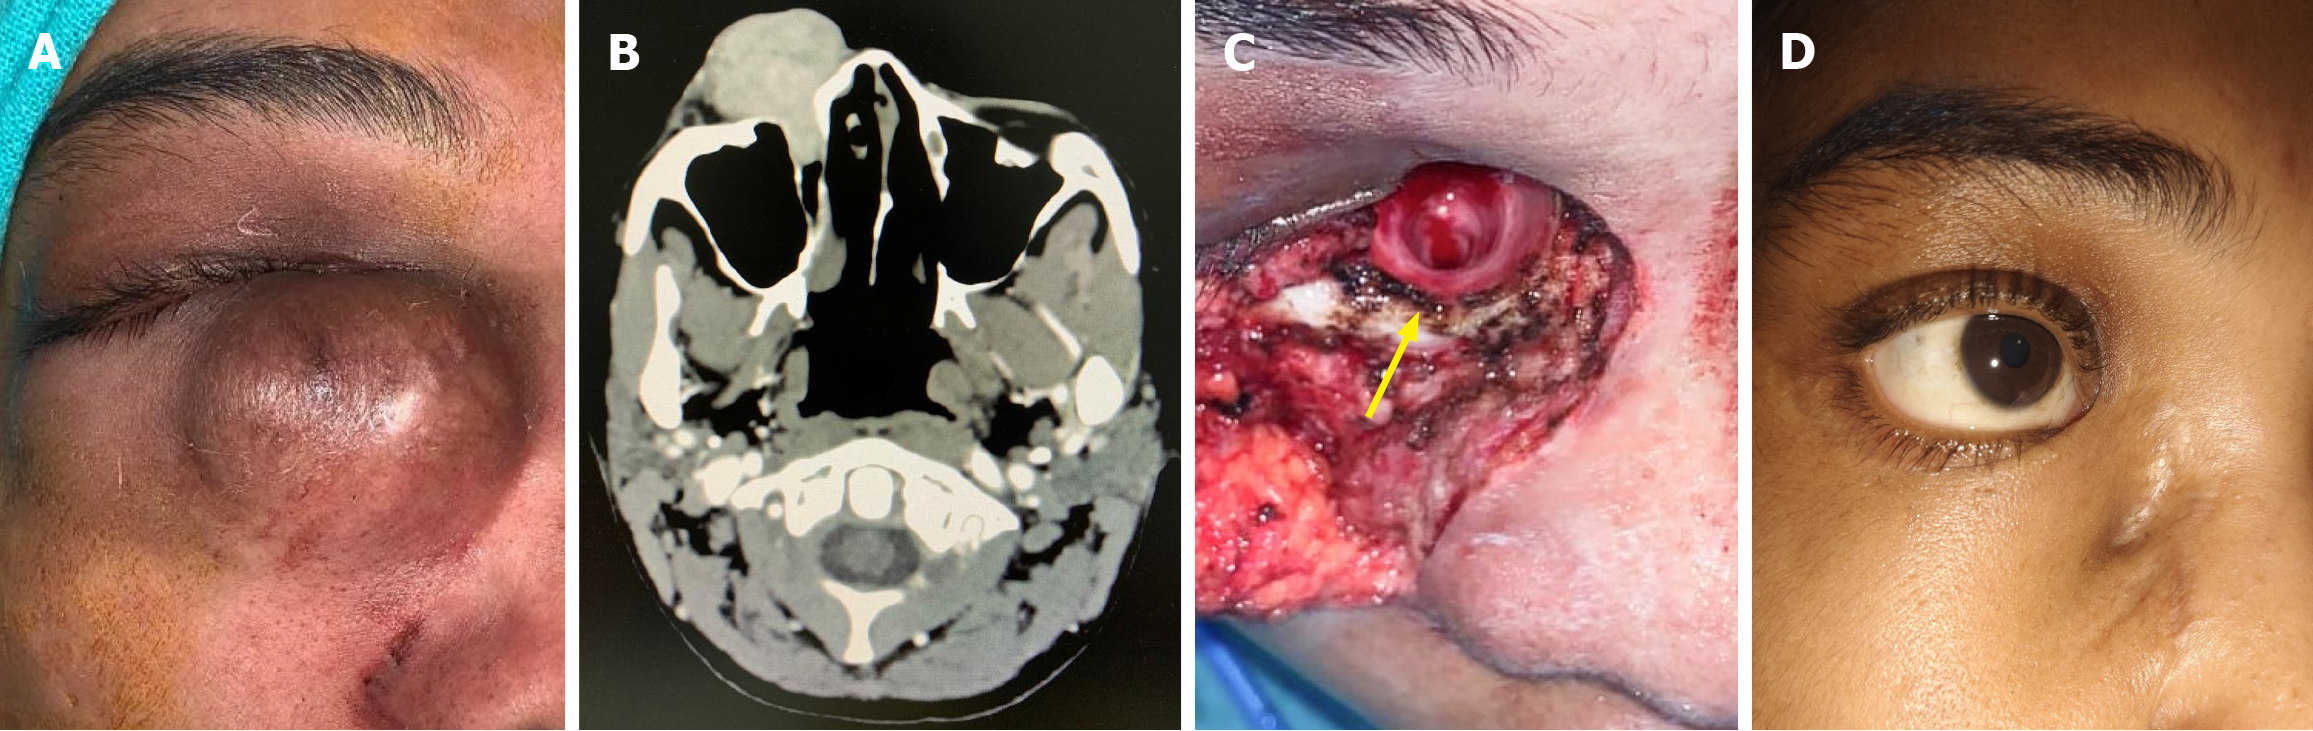

Figure 1 A case of recurrent dermatofibrosarcoma of lacrimal sac in a young female.

A: Clinical photo showing a medial canthal soft tissue mass extending to the nasolacrimal duct; B: Contrast-enhanced computed tomography of the face demonstrated a well-defined soft tissue mass extending from the medial canthus to the nasolacrimal duct, with canal dilation but no bony erosion or orbital extension; C: Intraoperative photo after tumor excision showing the grossly enlarged nasolacrimal canal (marked in yellow arrow); D: Clinical photo taken after 2 years of follow-up showing a depressed scar with acceptable cosmesis without any recurrence.